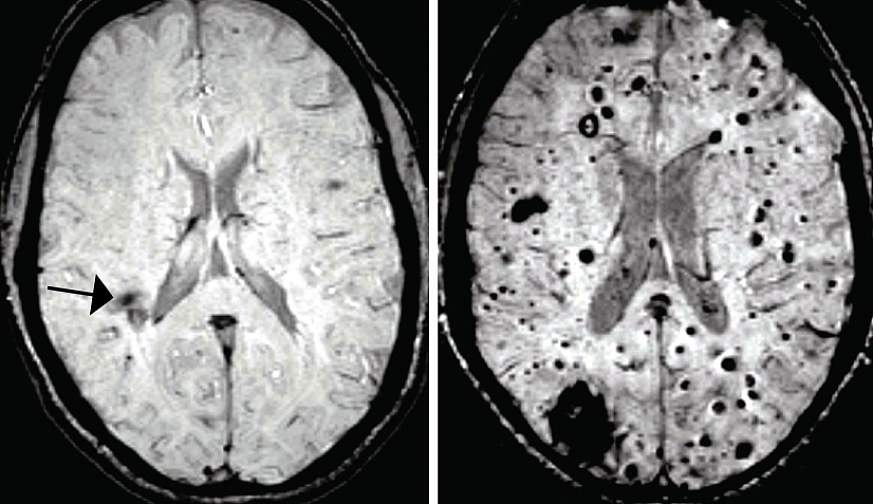

ناهنجاری های مغزی کاورنوس یا غار مانند (CCMs) دسته هایی از عروق خونی منبسط شده با دیواره های نازک شده هستند که میتوانند در هنگام نشت خون به بافت مغزی اطراف، باعث تشنج یا سکته شوند. تیمی از دانشمندان در دانشگاه پنسیلوانیا مکانیزم هایی را مورد بررسی قرار دادند که باعث تولید ضایعه های CCM در مغز موش هایِ مهندسیِ ژنتیک شده، میشوند؛ و سپس ارتباط غیر منتظره ای آن را با یک باکتری موجود در شکم پیدا کردند. زمانی که باکتری از بین رفت، تعداد ضایعات مذکور به طور چشم گیری کاهش یافت.

حال سوال اینجا بود که حضور این باکتری ها در جریان خون، چگونه میتواند رفتار عروق خونی مغز را تحت تاثیر قرار دهد. باکتری گرم-منفی، مولکول هایی با نام (lipopolysaccharides (LPS تولید میکنند که پتانسیل بالایی در فعالسازی سیگنال های طبیعی سیستم ایمنی دارند. زمانی که به موش ها، فقط LPS تزریق شد، تعداد زیادی ضایعات CCM بزرگ در مغز آنها شکل گرفت؛ درست شبیه مواردی که در عفونت باکتریایی ایجاد شده بود. در مقابل، زمانی که گیرنده های LPS (با نام TLR4) به صورت ژنتیکی در موش ها حذف شدند، دیگر ضایعه ای در مغز آنها ایجاد نشد. محققین دریافتند که در انسان ها نیز، جهش های ژنتیکی ای که باعث افزایش بیان TLR4 میشوند، با افزایش ریسک شکل گیری CCMs در ارتباط هستند.

محققان، تغییرات باکتری های بدن (میکروبیوم) را با دو روش بررسی کردند. اول، موش های مدل CCM را در شرایط عادی یا شرایط بدون میکروب پرورش دادند. دوم، به این موش ها آنتی بیوتیک داده شد که میکروبیوم آنها مجددا تنظیم شود. در هر دو حالت، هم تزریق آنتی بیوتیک و هم شرایط بدون میکروب، تعداد ضایعه ها به طور قابل ملاحظه ای کاهش یافت که نشان میدهد دو عامل کمیت و کیفیت میکروبیوم شکم میتواند در شکل گیری CCM ها تاثیرگذار باشد. در نهایت، دارویی که گیرنده های TLR4 را مسدود میکند، به طور چشم گیری، تشکیل ضایعات را کاهش داد. این دارو برای درمان عفونت منتشر خونی (سپسیس) مورد تست بالینی قرار گرفته است و اکنون نیز پتانسیل اثر درمانی آن در CCMs مشاهده شده است. با این حال تحقیقات زیادی در این زمینه باید انجام شود.